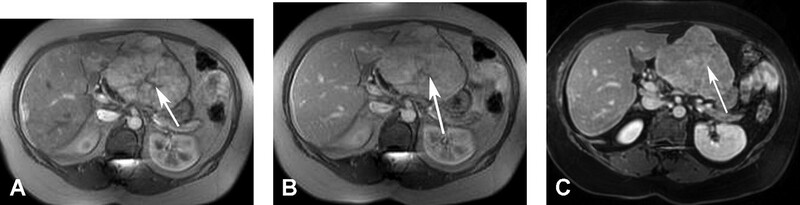

FNH có thể đồng hoặc tăng nhẹ tín hiệu trên T2W và đồng hoặc giảm nhẹ tín hiệu trên T1W. Sẹo xơ mạch tạo ra tín hiệu cao trên T2W, đây là đặc điểm duy nhất của FNH. Trêm MRI có tiêm thuốc tương phản, tương tự như CT, sẹo xơ-mạch có thể bắt thuốc không rõ ở thì động mạch với bắt thuốc chậm dần về sau, thấy rõ nhất ở thì muộn (Hình 7). Tuy nhiên, khối bao quanh sẹo xơ -mạch thờng bắt quang đồng nhất và mạnh ở thì động mạch, đồng hoặc tăng nhẹ tín hiệu so với gan xung quanh ở thì tĩnh mạch cửa và thì muộn. Các tổn thuơng nhỏ, <1-2cm, có thể bắt quang đồng nhất hơn và sẹo – xơ mạch không nhìn thấy được. Gd-ethoxybenzyl- DPTA (Gd-EOB-DPTA), một loại thuốc tương phản MRI hướng đến tế bào gan, có thể cho thấy bắt thuốc u ở thì ộng mạch sớm và ngấm thuốc vào tế bào gan tễ do ngấm thuốc bởi tế bào gan trong khối và bài tiết vào các ống mật dị hình dẫn lưu kém. Các thuốc dựa vào Manganese (mới có ở Mỹ) ngấm vào tế bào gan hoặc oxide sắt siêu thuận từ (SPIO) ngấm vào đại thực bào, trong FNH và làm xám tổn thương tương tự gan bình thường xung quanh. FNH có thể tăng ngấm sulfur colloid trong chụp nhấp nháy phụ thuộc vào tỉ lệ phần trăm tế bào Kupffer trong u.

Hình 7. Tăng sản nốt khu trú. Tổn thương bắt thuốc ở thì động mạch trên hình T1W 3D GRE (A) và và sẹo trung tâm còn lại không bắt thuốc (mũi tên). Ở thì tĩnh mạch cửa (B) và thì muộn (C) có lấp dần thuốc tương phản ở sẹo trung tâm (mũi tên).